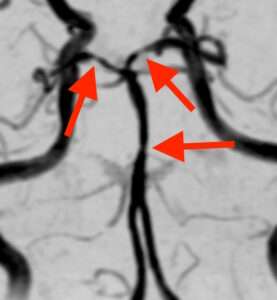

頭部MRA検査で脳の血管を撮影しました。

脳底動脈や後大脳動脈という血管が、所々くびれて細くなっています。

したがって、この症状の経過と画像所見から、可逆性脳血管攣縮症候群と診断しました。可逆性脳血管攣縮症候群は、排便のように息をこらえていきむ動作が誘因となります。また、咳やくしゃみ、笑う事、泣く事、歌を歌う事などで誘発される事もあります。1) 2)